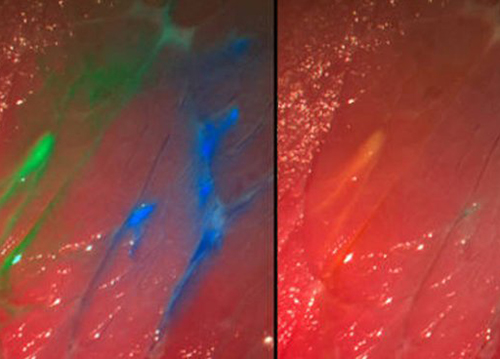

Зональное изображение делает границы окрашенных тканей более отчетливыми. В Институте производственной техники и автоматизации им. Фраунхофера (Маннхайм, Германия) разработана новая система визуализации, позволяющая видеть хирургу опухоль окрашенной на фоне здоровых тканей.

Разработанная система визуализации под названием Мультиспектральной интраоперативной передачи изображений в реальном времени позволяет совмещать несколько изображений с воспринимающей цвета камеры и эндоскопа. Камера блокирует определенные цвета спектра, что позволяет видеть окрашенные зоны более отчетливо.